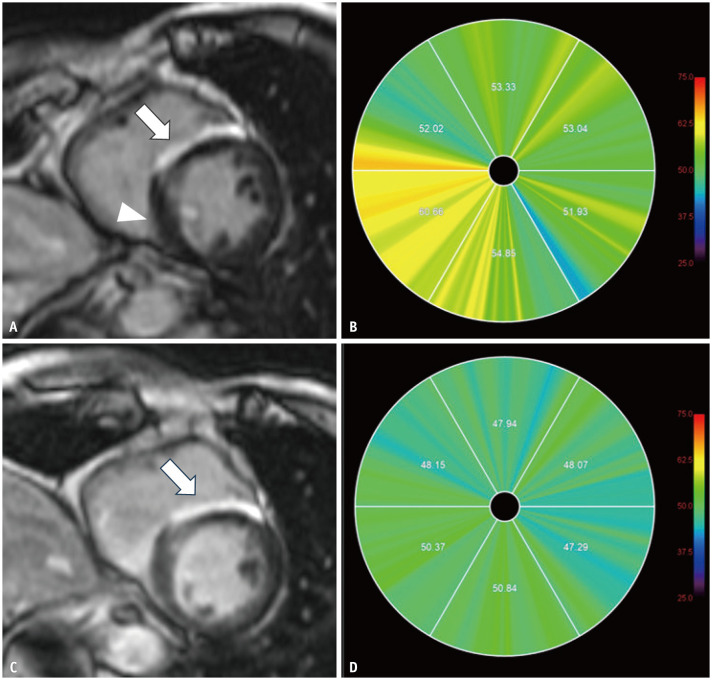

Cardiac sarcoidosis (CS) poses significant diagnostic and therapeutic challenges due to its heterogeneous clinical manifestations and the limitations of conventional diagnostic approaches. Advances in imaging modalities, particularly cardiac magnetic resonance imaging (CMR) and ¹⁸F-fluorodeoxyglucose positron emission tomography (FDG-PET), have revolutionized the evaluation and management of this complex condition. CMR, with its superior spatial resolution and advanced techniques such as late gadolinium enhancement, T1/T2 mapping, and extracellular volume quantification, offers unparalleled insights into myocardial structure and fibrosis. These techniques not only enhance diagnostic accuracy but also provide critical information on disease activity and treatment response. Among these, T2 mapping has emerged as a valuable marker for active inflammation, with high values reliably indicating acute disease states. FDG-PET serves as a complementary modality by detecting active granulomatous inflammation and guiding immunosuppressive therapy. The synergistic integration of CMR and FDG-PET provides a comprehensive approach to diagnosing and monitoring CS, enabling the identification of subclinical disease and the optimization of therapeutic strategies. Furthermore, the incorporation of quantitative biomarkers, such as strain metrics and T2 values, promises to refine disease assessment and management. These advancements have the potential to transform the paradigm of CS care, ultimately improving patient outcomes.